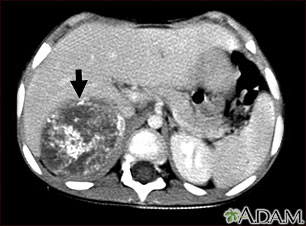

This CT scan of the upper abdomen shows a large tumor (neuroblastoma) on the person's right side (lower left side of picture). The tumor is behind the liver and is pushing the liver forward and may have possibly spread into the liver tissue.